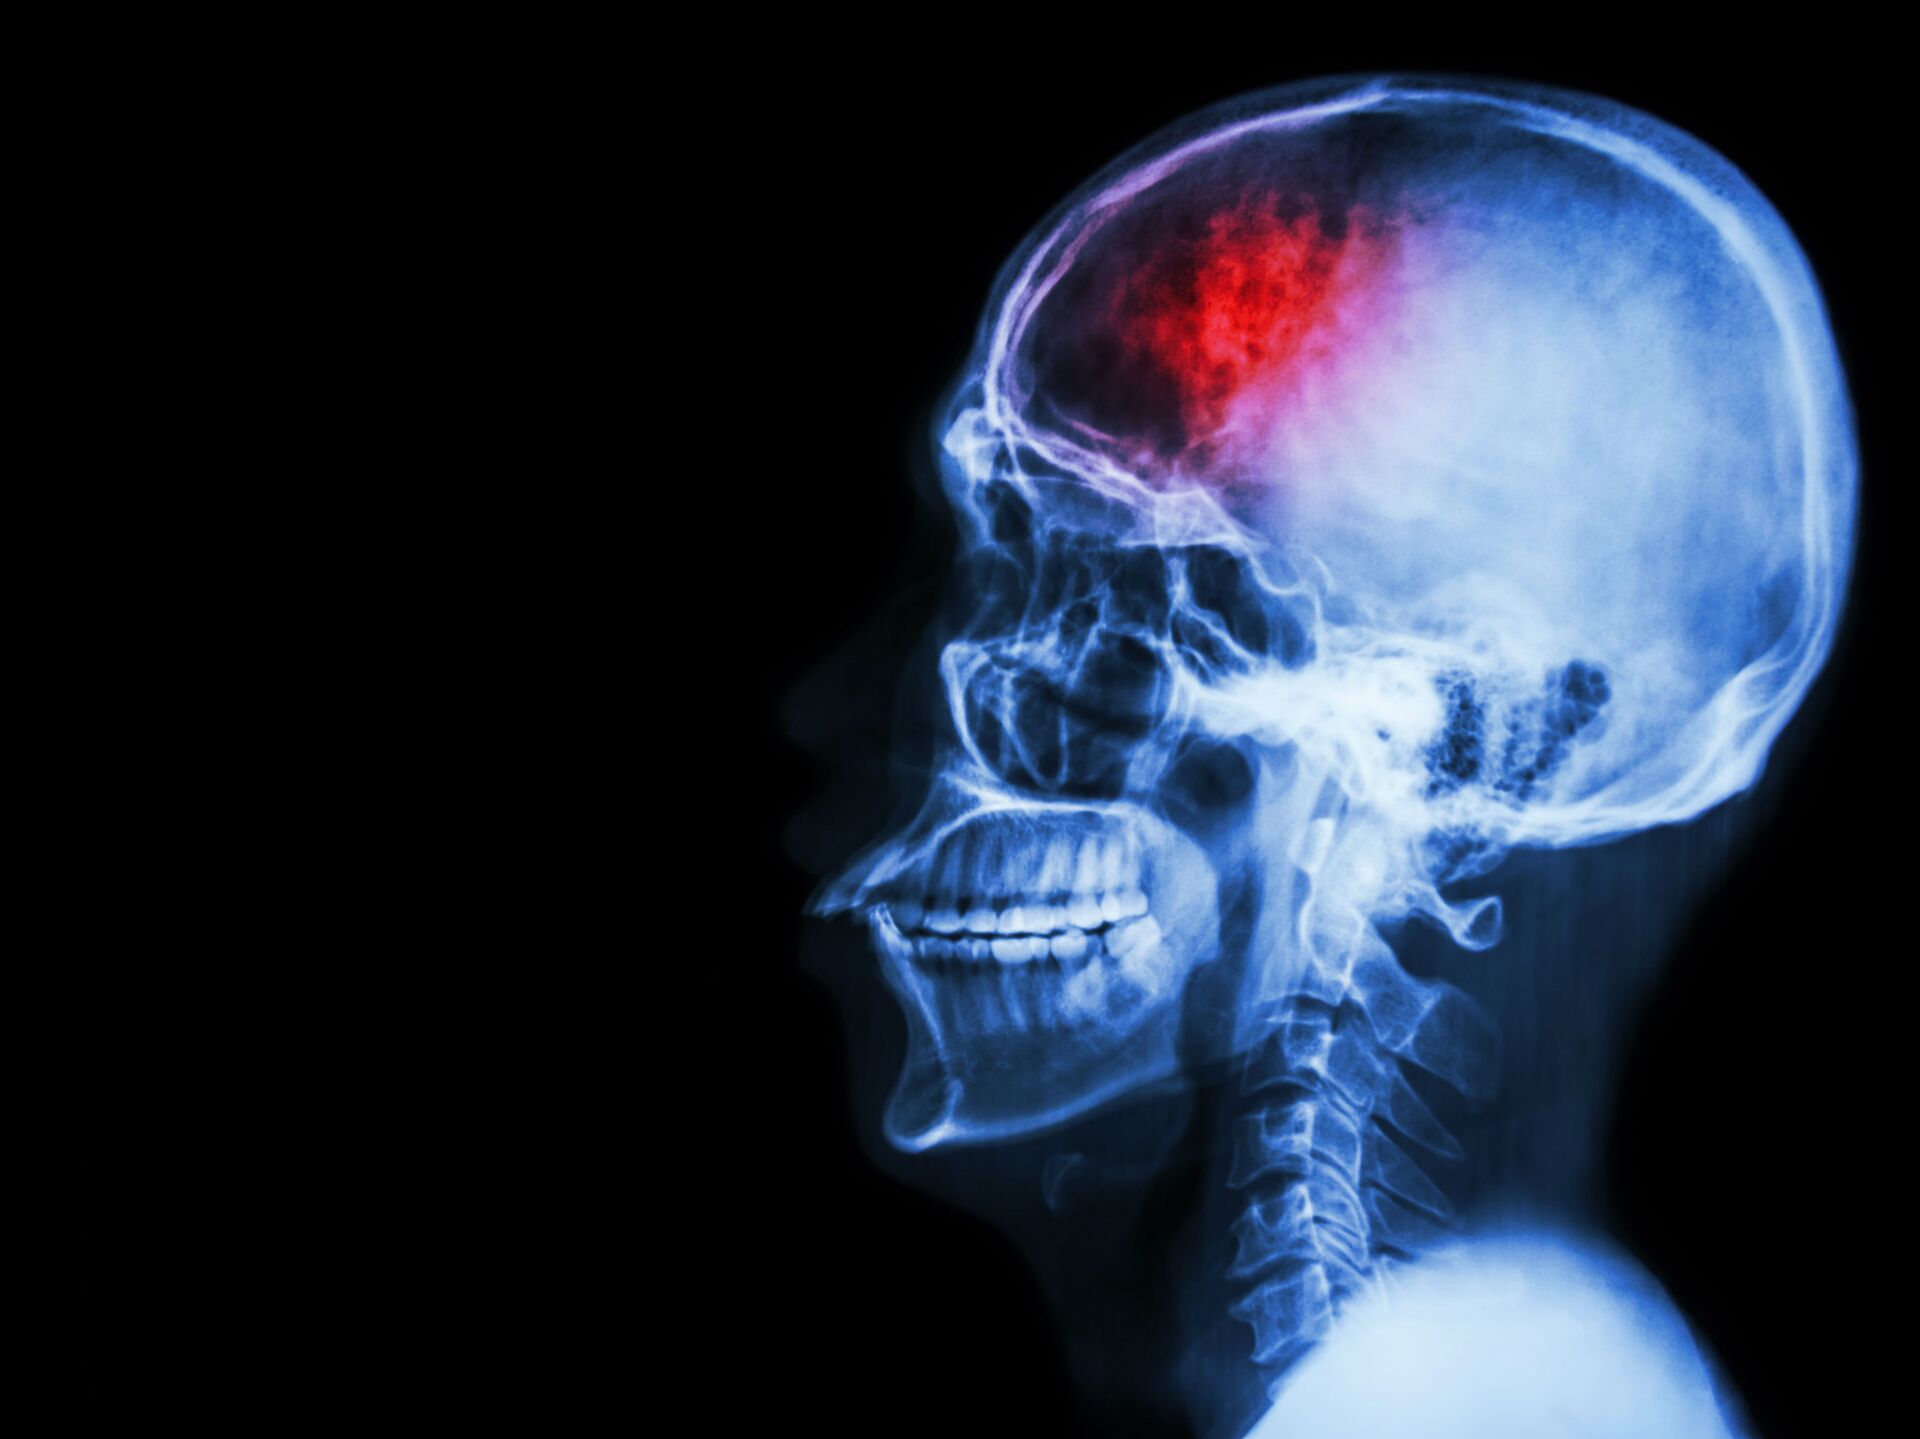

脳卒中の代替治療

標準的な脳卒中治療薬と併用した代替脳卒中治療は、特定の人々にさらなる利益をもたらす可能性があります。

脳卒中は、直ちに治療が必要な健康上の緊急事態です。